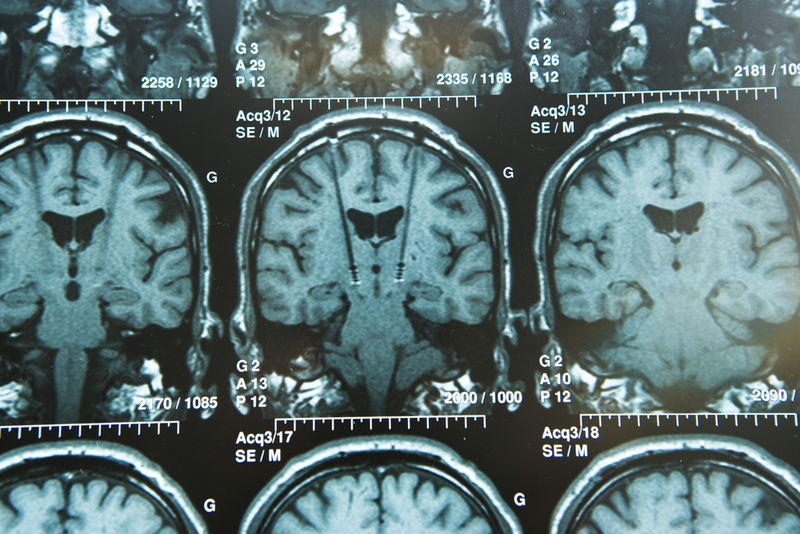

Accurate simulations could potentially help medical professionals forecast challenges and outcomes of treatment procedures for patients with schizophrenia. Dassault Systemes (Euronext Paris: #13065, DSY.PA) announced that National Institute of Mental Health & Neuro Sciences (NIMHANS), the apex centre for mental health and neuroscience education in India, has deployed Dassault Systemes' SIMULIA applications to predict the efficacy of Transcranial Direct Current Stimulation (tDCS), a non-invasive clinical treatment for schizophrenia patients, virtually before the clinical procedure.

NIMHANS's adoption of SIMULIA applications powered by the 3DEXPERIENCE platform is a first-of-its-kind deployment, where psychiatrists at NIMHANS will be able to leverage simulation technology to forecast challenges and outcomes of the treatment procedure for disorders such as schizophrenia. With SIMULIA applications, the team envisages the potential to develop a conceptual non-invasive method for Deep Brain Stimulation.

With multiphysics simulation capabilities on the 3DEXPERIENCE platform, under the WISER Neuromodulation Program at the National Institute of Mental Health and Neurosciences, patient-specific finite element models of the brain are used to accurately estimate the likely impact of electrical stimulation for treating the symptoms of schizophrenia, which, in turn can facilitate personalized neuromodulation.